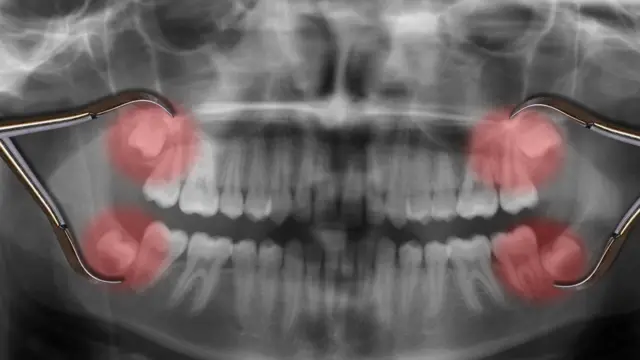

4. Dentes sisos ou 'do juízo'

Nós temos dentes com formatos diferentes porque eles desempenham distintas funções. Os incisivos, na frente da boca, ajudam a cortar pedaços de comida; os caninos, pontiagudos, rasgam alimentos mais desafiadores, como as carnes; e os molares servem para que a comida chegue a uma textura que possibilite a digestão.

Mas existe um tipo de dente sem o qual poderíamos viver bem: os sisos. Eles estão na parte traseira da mandíbula e se desenvolvem à medida que envelhecemos - por isso são conhecidos popularmente como "dentes do juízo". Eles geralmente aparecem quando chegamos à idade adulta.

Nossos ancestrais os usavam para mastigar plantas, mas hoje não precisamos deles.

O problema que geram é de espaço. Não temos lugar sobrando para eles em nossas mandíbulas, o que significa que eles geralmente empurram os outros dentes - e isso pode ser muito doloroso.

A razão de não haver espaço suficiente é fato de que o cérebro cresceu ao longo do tempo, modificando o formato da nossa cabeça.